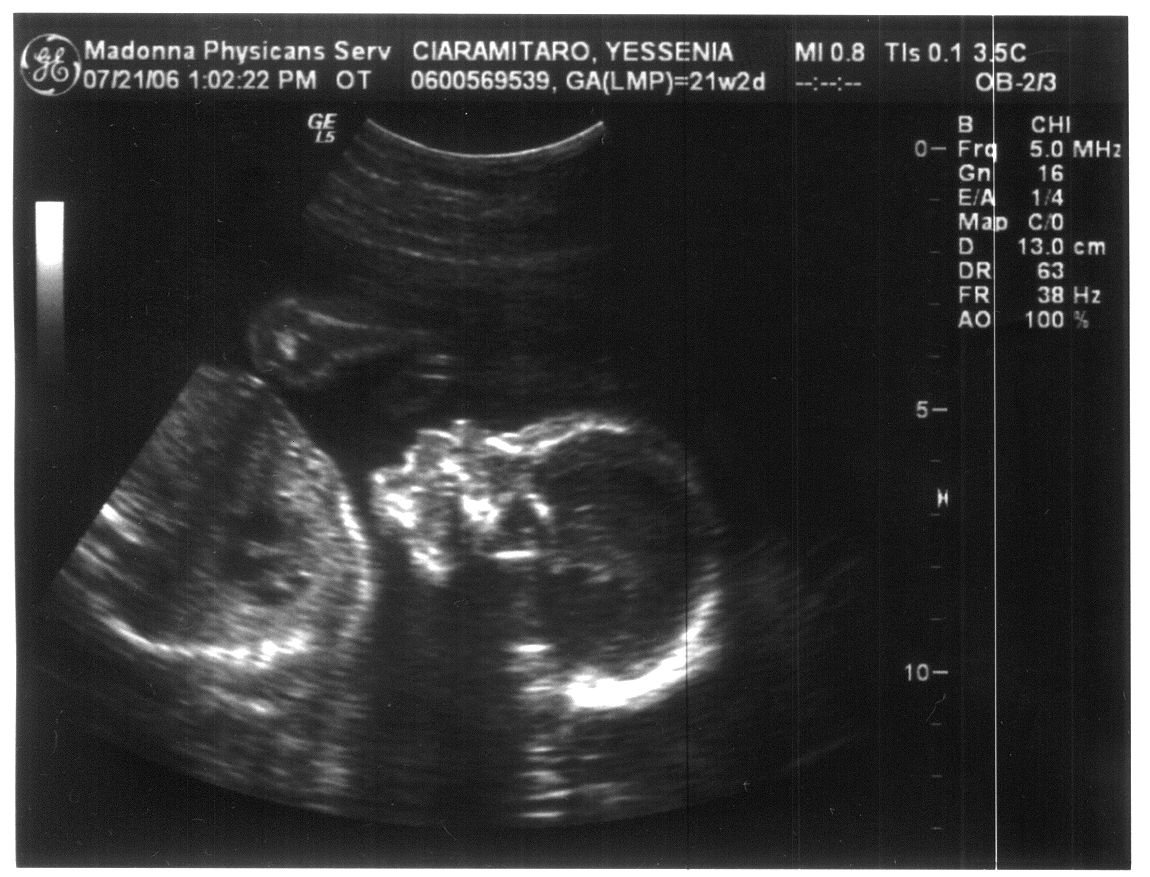

Last Modified On:March 2, 2015 5 PM Welcome to the future member of the Ciaramitaro clan!

Looks like our baby is coming bundled with a Skeleton Halloween Costume!